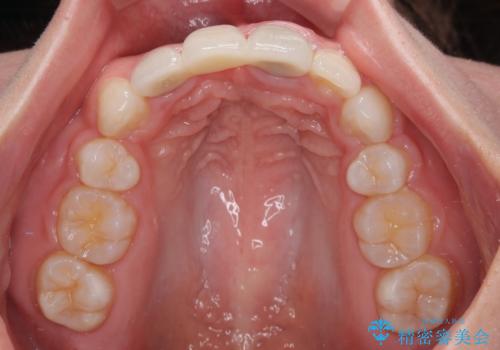

歯肉ラインを整えるために歯肉移植術を行うか悩んでいましたが、行わないという判断をされたため、やや不揃いの歯肉ラインとなりました。